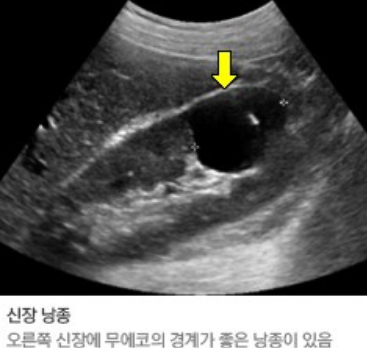

간의 실질 크기와 간내 혈관의 크기, 간의 미만성 또는 국소적 병소, 담낭 및 담관의 구조 및 확장 여부를 알 수 있고,